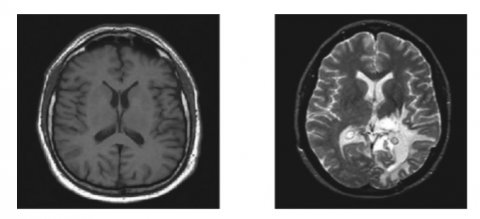

The BraTS dataset was developed as a standard for assessing and designing algorithms for segmentation and diagnosis of brain tumor. The brain tumor MRI scans are part of BraTS dataset collection which was collected from several institutes. Research organizations, hospitals and colleges are few of the institutions which contributed to the BraTs dataset. The patients gave their informed agreement whose MRI scans were used to create the BraTs dataset to have their medical information used for research. The images were taken from the challenge hosted by B. Menze et al. MICCAI 2012 [50]. These photos were used in the study by the aforementioned researchers. Figure 8 shows the MR images of normal and abnormal brain tissues. The competition was a direct outcome of the research conducted by these academics. The image database for the challenge now includes content from scholarly organizations. The MICCAI 2012 Competition on Multimodal Brain Tumor Segmentation is the name of the competition. This held a competition called Multimodal Brain Tumor Segmentation (BRATS) competition in connection with MICCAI 2012 conference. The conferences as well as tournament are being held at the same venue. The goal of this competition is to compare and contrast the various approaches being studied for automated brain tumor segmentation. Thirty distinct patients with a diagnosis of glioma have had their multi contrast MR images used as the training set.

(a)                                                                 (b)

Figure 8. (a) MRI of normal brain (b) MRI of abnormal brain

There is a wide spectrum of severity among those who have had or been treated for surgical resection. Expert opinions on matters like "active tumor" and "edoema" are also included. All patients have access to magnetic resonance (MR) scans in T1, T2, and FLAIR formats, in addition to post-gallium T1 imaging. Data was extrapolated to a resolution of 1 mm in each direction after the skull was removed using linear co-registration of all volumes with the T1 contrast image. This was done to guarantee the highest level of realism in the final product. This was done so that the final product would be as accurate to life as possible. Not a single effort was made to compile the many happenings into a central hub from which they could be studied and understood more readily.